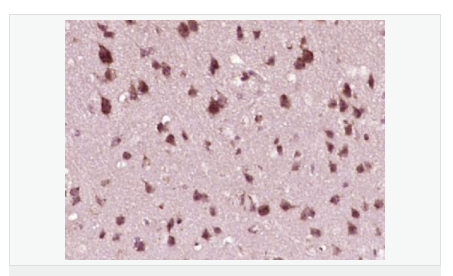

產品應用WB=1:500-2000 ELISA=1:5000-10000 IHC-P=1:100-500 IHC-F=1:100-500 Flow-Cyt=1ug/test ICC=1:100-500 IF=1:50-200 (石蠟切片需做抗原修復)